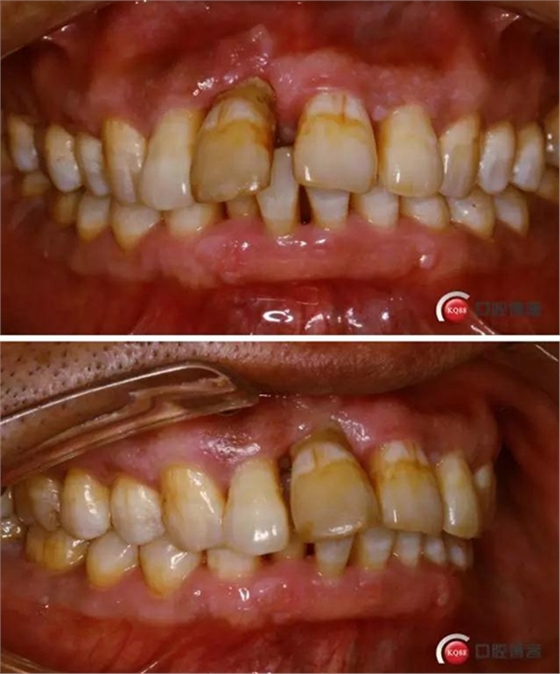

術(shù)前口內(nèi)照